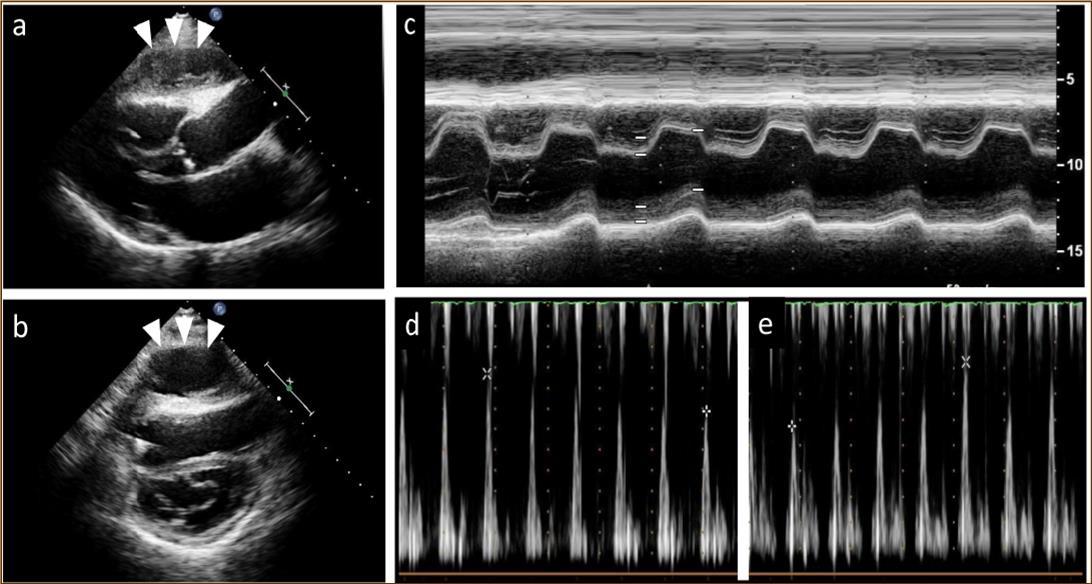

At 2 years post-HTx, when the patient first developed ACR, echocardiography revealed mild pericardial effusion, but there was no deterioration in hemodynamic parameters compared with the findings noted on previous examinations. ACR was considered as the cause of mild pericardial effusion and the dose of immunosuppressive regimens were increased. Two months after that, pericardial effusion persisted even though resolution of ACR was confirmed on EMB. At 2.5 years post-HTx, echocardiography revealed paradoxical septal motion and a large cystic-like mass with a thick capsule adhered to the right ventricle (Figure 1a, b). Roughly from that time, the patient began to experience dyspnea on mild exertion and lower leg edema. Oral diuretics were added to the prescription to relieve symptoms but dyspnea and edema did not resolve entirely.

Figure 1.Echocardiography findings. A large cystic-like mass with a thick capsule was found in front of the the right ventricle (white arrows) (a. long axis view; b. short axis view). Paradoxical septal motion were seen in a motion mode image of left ventricle (c). Respiratory variation in both mitral (d) and tricuspid inflow velocities (e) were seen.

At the age of 52 years, the patient was admitted to our institution for both evaluation of heart failure and regular right heart catheterization including EMB. With respect to allograft rejection, ACR was again detected on regular EMB, and the immunosuppressive regimens were strengthened. Further echocardiographic investigations were conducted to explore the implications of findings indicative of constrictive physiology with thickened pericardium. Respiratory variation in both mitral and tricuspid inflow velocities was seen, but these findings did not meet the complete criteria for CP diagnosis (Figure 1c-e). Magnetic resonance imaging of the heart revealed seroma and a thick cystic-like capsule tightly adhered to the right ventricle (Figure 2a, b). Right heart catheterization revealed elevation of right atrial pressure with severely reduced cardiac index (Figure 3a). The classic dip-and-plateau pattern of right ventricular diastolic pressure and equalization of right atrial pressure and right ventricular diastolic pressure were also observed (Figure 3b). Based on these results, effusive CP or cardiac tamponade-like hemodynamics were strongly suspected, although the etiology remained unknown. Therefore, at 3 years post-HTx, the patient initially underwent removal of the seroma through exploratory lateral thoracotomy to elucidate the etiology of the disease. Yellowish fluid was found and the fluid was completely aspirated. Immunosuppressive regimens including everolimus, which may interfere wound healing, were temporarily converted to standard three-drug regimens. Removal of the seroma via lateral thoracotomy did not lead to improvement in symptoms or hemodynamics. Pathological analysis revealed fibrin and seroma, but no malignant cells or infection. Since the initial procedure did not have any effect on the patient’s symptom, pericardiectomy through median sternotomy was performed at two months after the initial procedure. Intraoperative findings indicated a thickened pericardium and effusion in front of the right ventricle. At first, after sternotomy and adhesiotomy, the tissue in front of the right ventricle, which appeared to be thickened parietal pericardium, was completely resected and the effusion fluid was removed. However, high central venous pressure (20 mmHg) persisted, resulting in a displacement of the left ventricle by the right ventricle. Therefore, additional tissue from the front of the right ventricle was excised, corresponding to diffusely thickened visceral pericardium and epicardium. After the procedure, central venous pressure decreased from 20 to 10 mmHg, and displacement of left ventricle resolved. Pathological analysis of the resected tissues demonstrated chronic fibrosis and chronic inflammation with plasma cells, but no infectious etiology was identified (Figure 4 a, b). After the pericardiectomy, hemodynamics (Figure 3a, c) and symptoms improved, and the patient is currently experiencing a favorable clinical course without complications.